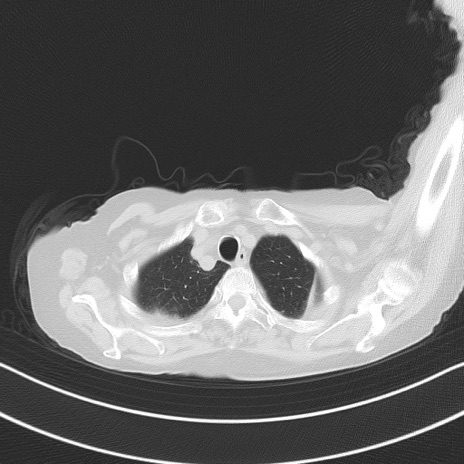

冠状断像